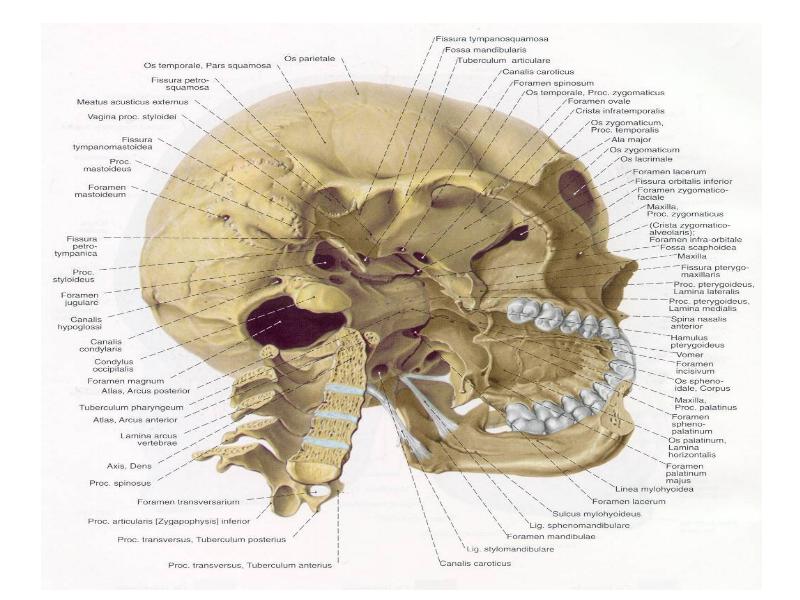

Анатомия и особенности фиссуры петротимпаника